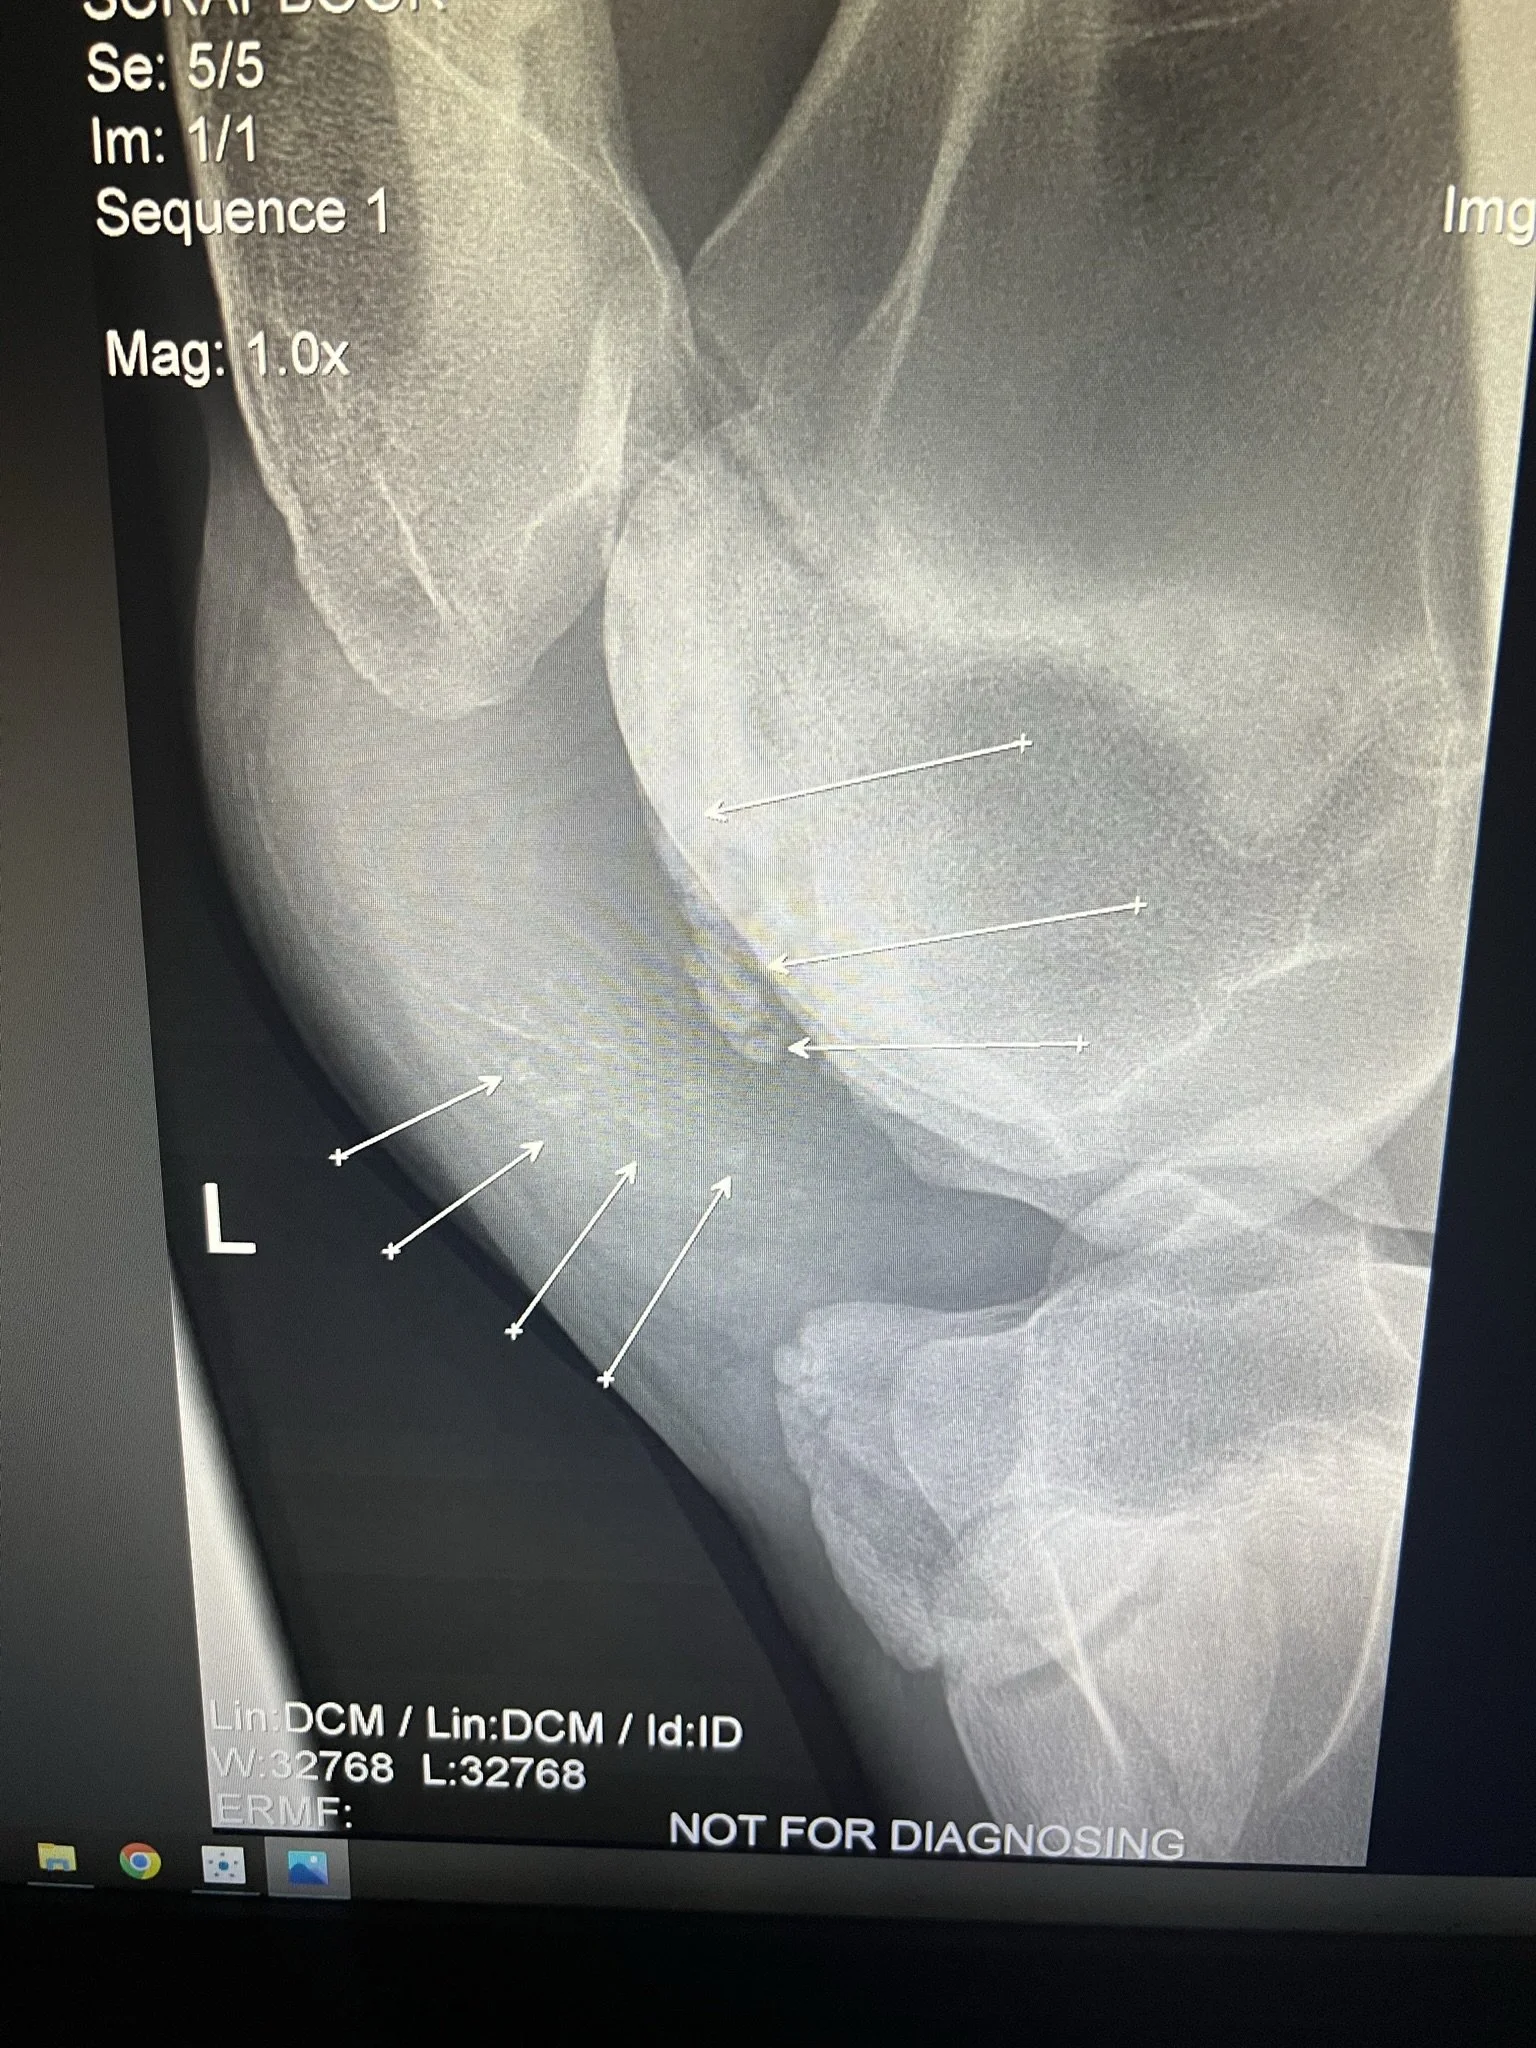

He still needed to be gelded, so while he was under anesthesia, we also did X-rays on his stifles (knees) to see the extend of his condition. He was very sore and slightly lame on his back left leg and had a large swelling/mass on the stifle as well. It turns out he had a whole bunch of bone fragments/cartilage floating around in his stifle (knee). He went up to NH to a specialist for surgery to remove the fragments. Because he had just been gelded, we opted to wait a few weeks for that to heal before we do the stifle surgery. The gelding site and the stifle surgery site would be very close together and have a high risk of any bacteria from that incision to go into the new surgery site. This would cause a bad infection and because they would be working on his bone, it would be a bone infection which is very difficult to heal.

Unfortunately all that proper food and hay with proper vitamins and minerals really made him grow. Normally we would be eastatic! He was finally starting to look like a horse and not a sickly baby moose. In a year, he went from a 15.3hh scrawny thing to a 17.3hh giant! Because of such a rapid growth, he developed more fragments in his stifle. This is nothing we could have avoided, it is just his body growing far faster than his bones.

So a year after his first surgery he went back for his second surgery on the same stifle for the same reason. The staff was happy to have him back and were shocked at how he grew! He had another successful surgery and made a full recovery back to 100%. Although he will probably need some joint injections in that stifle periodically throughout his life, he is 100% sound and loves to run around!